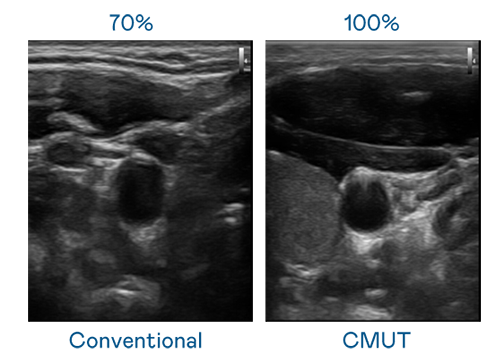

CMUT 技術是一種用電容式微機電元件來產生超音波訊號的技術。與傳統 PZT 壓電式技術相比,CMUT 頻寬增加 30%,更寬頻的超音波訊號讓影像解析度大幅提升,是實現高影像品質醫療超音波掃描、促進精準醫療發展的關鍵技術。

超音波影像的解析度高低,首先取決於探頭能發出的訊號頻寬。华体汇官网登录入口 CMUT 可提供高清晰的超音波訊號,提供高頻寬、高靈敏度、影像紋理細節更高的超音波影像,協助醫護人員縮短影像判讀時間及利用精準的醫療影像進行診斷。